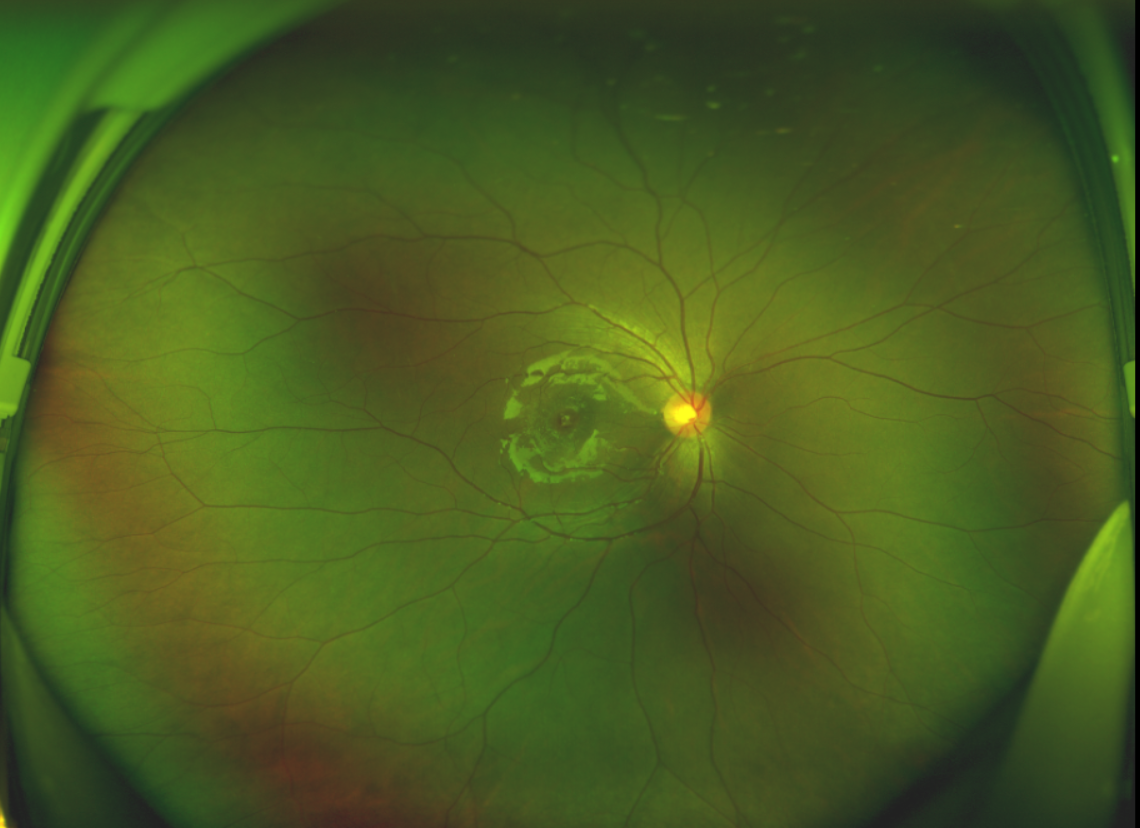

半年前的一次意外,誠(chéng)誠(chéng)(化名)右眼不慎受傷導(dǎo)致黃斑裂孔。從此,他的“視”界不再清晰,也不再有直線(xiàn)條……

黃斑位于視網(wǎng)膜正中心,是視覺(jué)最敏銳的區(qū)域,堪稱(chēng)“眼底的心臟”,負(fù)責(zé)我們閱讀、駕駛、識(shí)別人臉等精細(xì)視覺(jué)。 當(dāng)黃斑區(qū)的神經(jīng)組織出現(xiàn)全層缺損,形成一個(gè)“孔洞”,即為黃斑裂孔,它會(huì)直接導(dǎo)致中心視力急劇下降、視物變形、視野中心出現(xiàn)暗區(qū)。

由于裂孔較小,當(dāng)?shù)蒯t(yī)院建議先觀察,看看裂孔是否能夠自愈。可半年時(shí)間過(guò)去了,誠(chéng)誠(chéng)傷眼的裂孔不僅沒(méi)有愈合的跡象,反而越來(lái)越大,這讓家長(zhǎng)的心揪得更緊了。

經(jīng)過(guò)詳細(xì)的檢查和評(píng)估,王曉波主任決定采用“內(nèi)界膜翻轉(zhuǎn)覆蓋聯(lián)合粘彈劑固定術(shù)”為誠(chéng)誠(chéng)進(jìn)行治療。

除此之外,利用自體組織覆蓋為黃斑裂孔提供了理想的愈合環(huán)境,裂孔閉合速度顯著快于傳統(tǒng)方法。誠(chéng)誠(chéng)接受手術(shù)24小時(shí)后,檢查可見(jiàn)內(nèi)界膜瓣位置良好;術(shù)后1個(gè)月,黃斑裂孔已經(jīng)閉合,視力恢復(fù)到0.5;術(shù)后兩個(gè)月,視力進(jìn)一步提升到0.7。